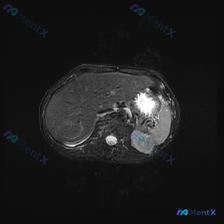

这是一张腹部横断面MRI,从信号特征看(胃腔内高信号内容物、腹主动脉流空低信号),更像是压脂后的T2加权像(T2WI),而非标准T1加权像。

✅ 肝脏:信号均匀,轮廓光整,无明显异常信号灶

✅ 脾脏:位于左侧,信号均匀,未见肿大或局灶性病变(这是核心阴性结果)

✅ 肾脏:皮质髓质结构可分辨,无明显异常

✅ 腹膜后:腹主动脉周围无肿大淋巴结

⚠️ 胃部:胃体部可见,胃腔内充满明显高信号影(在压脂T2WI中通常代表液体/胃液)

- 解剖毗邻干扰:脾脏紧邻胃底,图像左侧的高信号胃内容物(积液)非常显眼,非专业人士很容易把“高信号的胃”当成“脾脏的高信号病灶”

- 序列认知偏差:如果误把压脂T2WI当成T1WI,会对“液体高信号”产生错误解读(T1WI上液体通常是低信号)

- 视觉误差/解剖定位混淆(最可能):高信号胃内容物被误判为脾脏病变

- 支持点:胃腔紧邻脾脏、压脂T2WI中液体呈高信号、脾脏本身完全正常